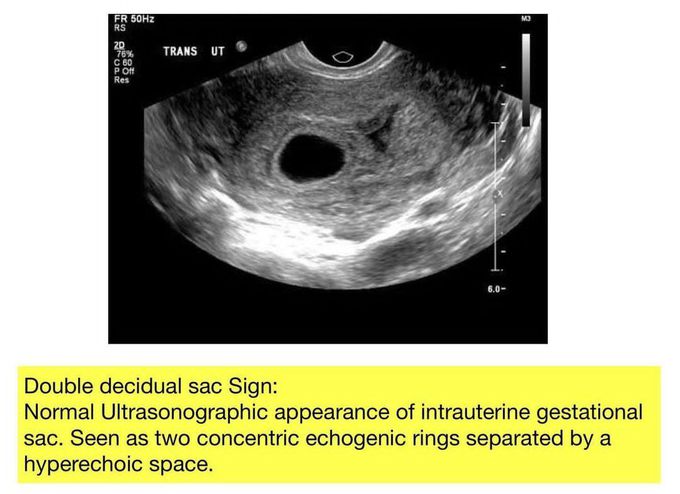

Double Decidual Sac Sign

Here is a review of the double decidual sac sign.